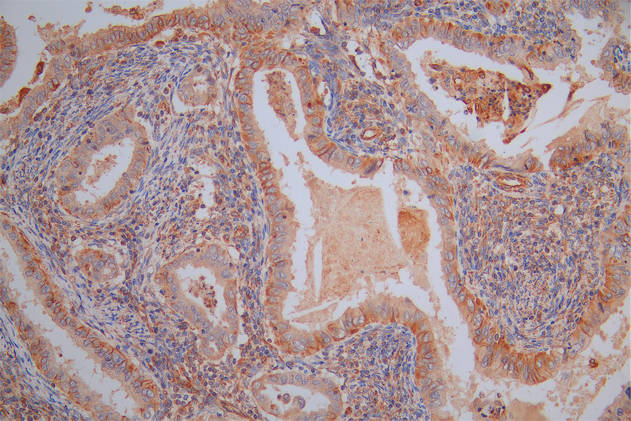

Immunohistochemistry of paraffin-embedded human pancreatic cancer using CSB-PA01567A0Rb at dilution of 1:100